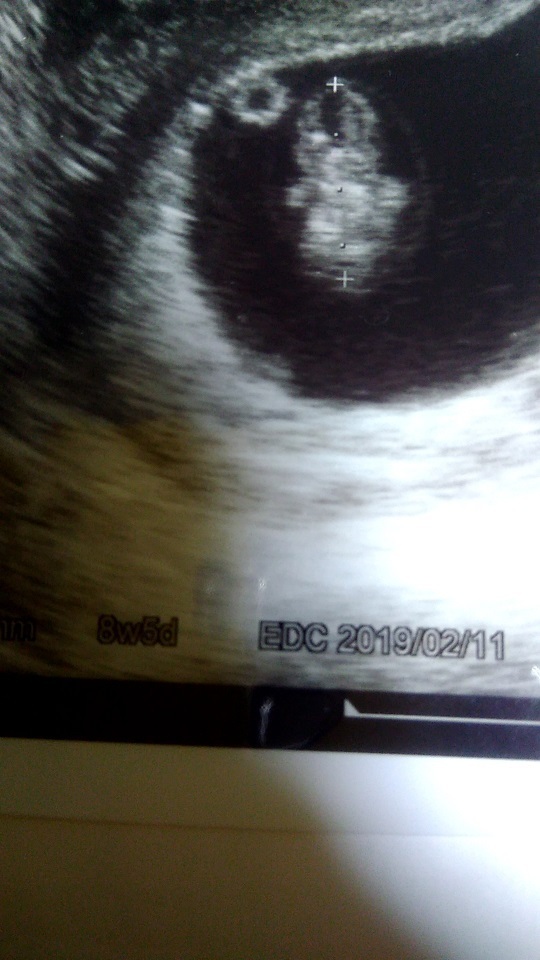

8週5日(8w5d・女の子)|ももあ さん(26歳)

エコー写真撮影時のエピソード:

初めて頭、体、とわかるようになった写真でした。自分のお腹の中に人として育っているんだなと実感することができました。

この時は赤ちゃんはそんなに大きく成長していないのに体重増加がひどく、先生に怒られ、太りすぎないように夫婦でジョギングを始めるきっかけになりました。

ジョギングを通して今まで以上に夫婦で会話をする機会も増えました。赤ちゃんに素敵なきっかけをもらったなと感じています。